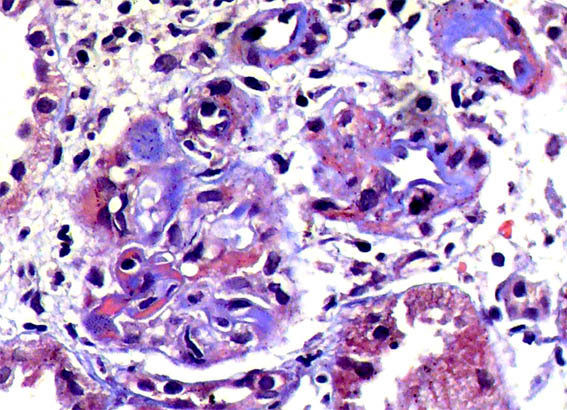

Figure 2. H&E, X400.